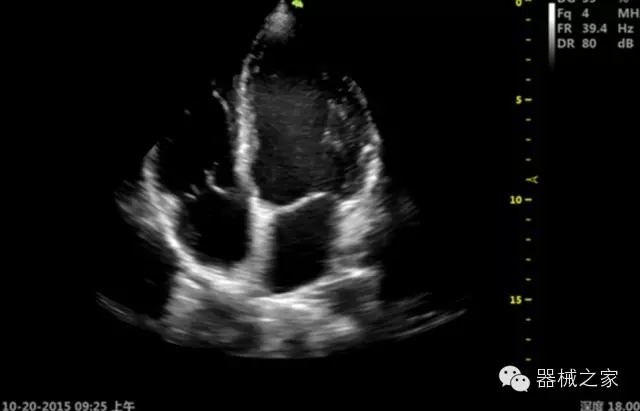

臨床圖片賞析

·移植S40高端臺(tái)式彩超高端平臺(tái)技術(shù),滿足超聲科腹部、淺表、婦產(chǎn)科、心血管、肌骨等應(yīng)用,提供超聲科完美解決方案;

·心功能綜合指數(shù)(TEI指數(shù)):用于左、右心室整體心臟收縮舒張功能評(píng)估的測(cè)量方法;

·全方位可調(diào)M型:有利于更好的觀察心腔大小及室壁階段性運(yùn)動(dòng)的異常情況;

·組織多普勒成像(TDI):TDI可定量評(píng)價(jià)心肌運(yùn)動(dòng),判斷是否有局部病變,還可評(píng)價(jià)早期的舒張功能;